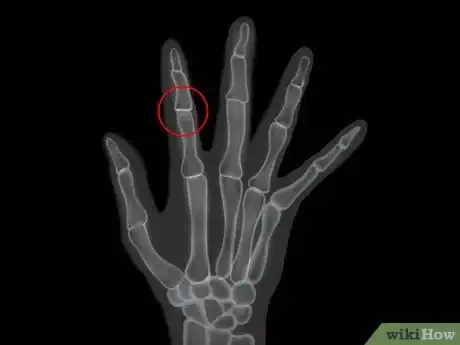

3Learn how rheumatoid arthritis is diagnosed. Rheumatoid arthritis is diagnosed using your signs, symptoms, medical and family history along with a physical exam. Your doctor will then use the diagnosis to create a treatment plan, with the primary goal being reduction of the pain by reducing inflammation and minimizing any damage to the joints.[29] To diagnose rheumatoid arthritis, your doctor will do:

- Lab tests, including x-rays or other imaging of the affected joints

- Blood samples, specifically one to examine blood for Rheumatoid Factor (RF) and other non-specific tests. The RF test can diagnose rheumatoid arthritis, while the non-specific ones indicate underlying inflammation.[30]

- Diagnostic tests to rule out other conditions that mimic rheumatoid arthritis, such as infectious arthropathies (painful joints from infection), Systemic Lupus Erythematosus (SLE), ankylosing spondylitis (which primarily affect the spine and larger joints), and fibromyalgia.[31]